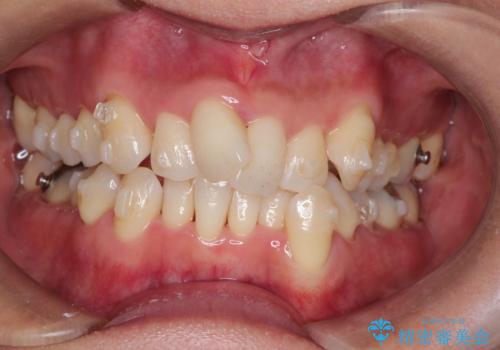

重度のガタガタのインビザラインによる非抜歯矯正

- 上下の歯のガタガタを主訴に来院されました。

インビザラインで奥歯を後方に移動させるのと、歯と歯の間をわずかに削ることでスペースを作り、歯を並べる計画としました。